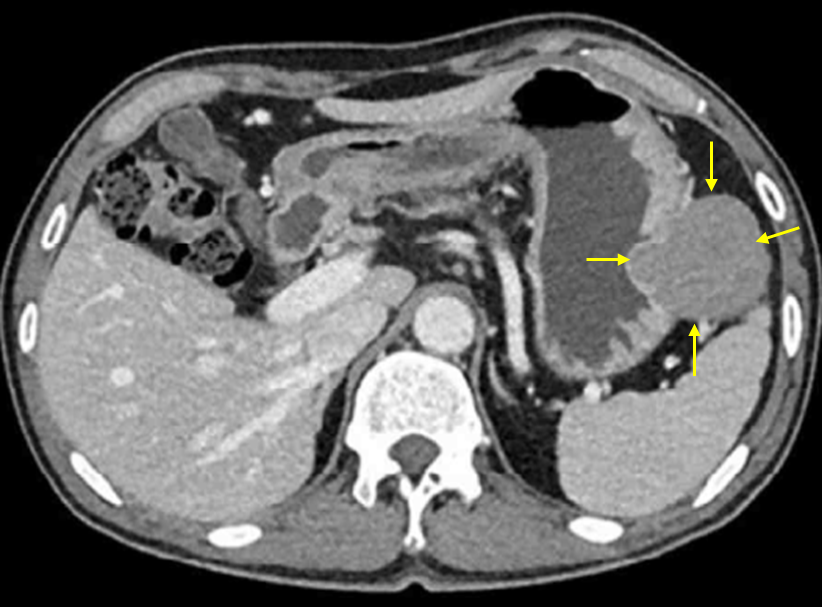

Img | CT: Gastric mass at submucosal layer |

Stomach mass가 있으나 매끈한 mucosal surface가 확인되며 CT상 submucosal area에 있는 것이 확인되므로 GIST 진단 하, wedge resection을 시행한다.

• CT상에서도 greater curvature에 submucosal area에서 기원하는 것처럼 보이는 tumor가 확인되고, 이 또한 GIST를 시사한다.